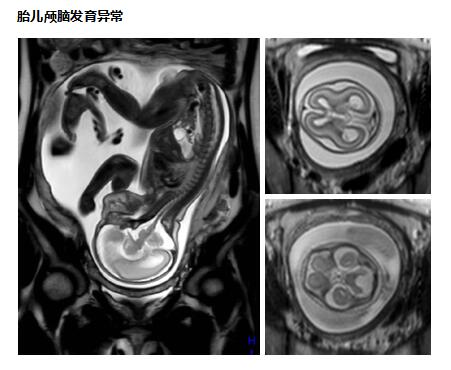

中枢神经系统应用

可应用于颅内外肿瘤性病变,脑卒中病变、血管性病变、感染性病变、外伤性病变,脑白质病变,先天性发育异常、退行性病变等中枢神经系统疾病检查,尤其是脊柱及脊髓病变,同时可以全脊柱成像,整个脊柱及脊髓病变一览无余,无处藏身。